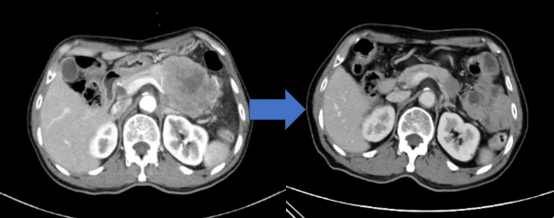

图8

66岁男性患者,因胰腺体尾部巨大占位入院,穿刺活检提示大细胞型神经内分泌癌(左图),予IP方案(伊立替康+卡铂)新辅助化疗6次,肿瘤显著缩小(右图),降期成功并行根治性手术。